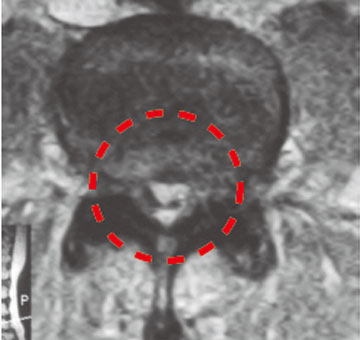

术后MRI影像可见,椎间管扩大,神经走向明显畅通